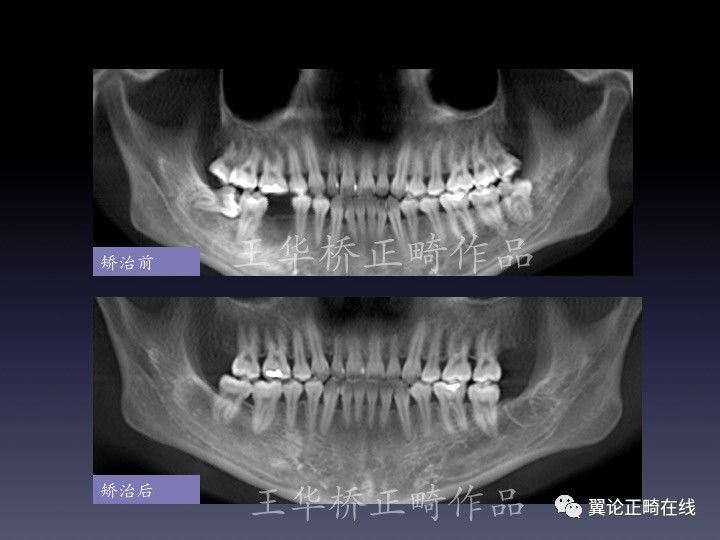

病例展示